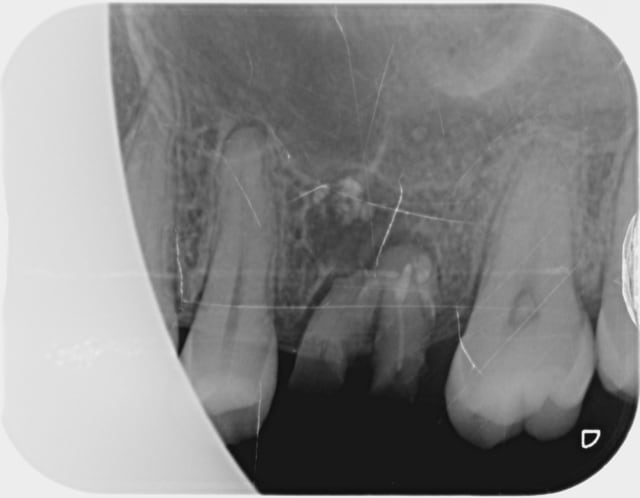

J'ai accueilli cette patiente un peu phobique , fait une anesthésie , une avulsion , un curetage de l'alvéole qui contenait de la pâte canalaire , le tout avec application de façon à ne pas pénétrer le sinus , vérifier une possible CBS , et suturer le tout .